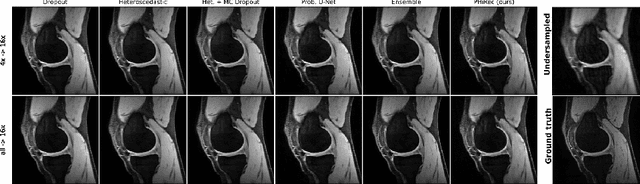

Abstract:MRI reconstruction techniques based on deep learning have led to unprecedented reconstruction quality especially in highly accelerated settings. However, deep learning techniques are also known to fail unexpectedly and hallucinate structures. This is particularly problematic if reconstructions are directly used for downstream tasks such as real-time treatment guidance or automated extraction of clinical paramters (e.g. via segmentation). Well-calibrated uncertainty quantification will be a key ingredient for safe use of this technology in clinical practice. In this paper we propose a novel probabilistic reconstruction technique (PHiRec) building on the idea of conditional hierarchical variational autoencoders. We demonstrate that our proposed method produces high-quality reconstructions as well as uncertainty quantification that is substantially better calibrated than several strong baselines. We furthermore demonstrate how uncertainties arising in the MR econstruction can be propagated to a downstream segmentation task, and show that PHiRec also allows well-calibrated estimation of segmentation uncertainties that originated in the MR reconstruction process.